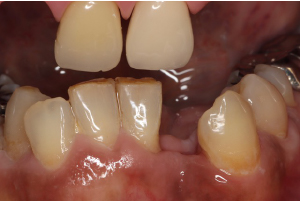

症例

ジルコニアブリッジ・セラミック矯正

治療前

治療後

左上1番は歯周病が進行し動揺がありました。また左上1番と2番の間には大きなスペースがありました。まず、歯周治療から始め、最終的には右上1番から左上2番まで3本ジルコニアオールセラミックで連結し、審美性、機能性を回復しました。